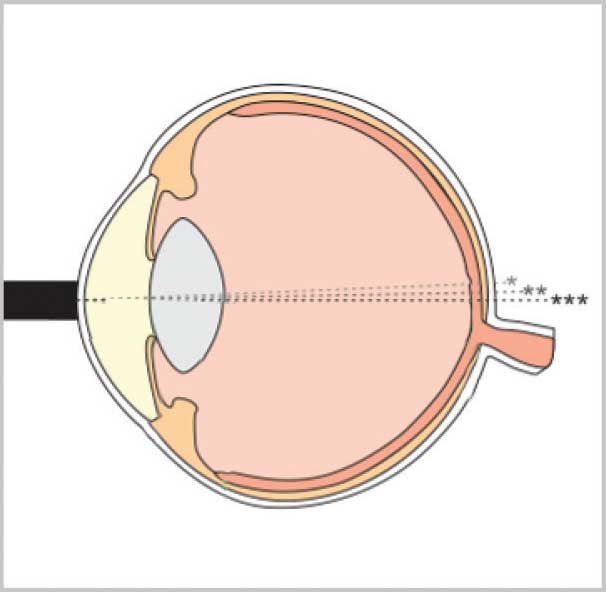

Унікальні функції керування вимірюванням Flex A-Scan допомагають досягти оптимальних значень вимірювань. Ці функції дозволяють користувачеві зосередитися на техніці застосування, в той час як програмне забезпечення приладу виконує аналіз форми хвилі в реальному часі і надає негайний зворотний зв'язок користувачеві.

Унікальний алгоритм оцінювання автоматично класифікує вирівнювання датчика вздовж осі вимірювання. Ранжування відбувається миттєво, і кожному якісному вимірюванню присвоюється 1 зірка, 2 зірки або 3 зірки (3 зірки означають найкраще вирівнювання).

Flex A-Scan може працювати в контактному або занурювальному режимі. Датчик випускає ультразвукові імпульси у воду (а не безпосередньо в око). Імпульси поширюються через воду і потрапляють у тканини. Цей метод вимірювання усуває потенційну деформацію геометрії рогівки, спричинену прямим контактом з датчиком.